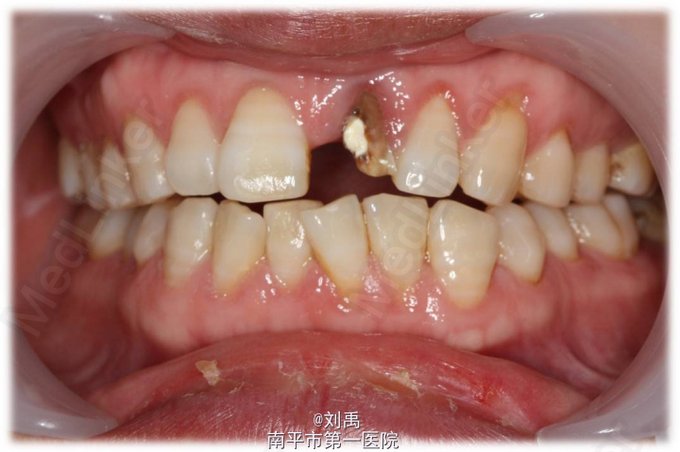

主诉:前牙缺损,要求修复 现病史:患者两月前左上前牙缺损,于我院行牙体治疗,近来我科要求修复。

21牙根管内可见充填物,根尖周无明显异常。

诊断:残冠 切龈后,预备桩道,植入纤维桩,牙体预备,比色,戴暂冠,复诊戴牙